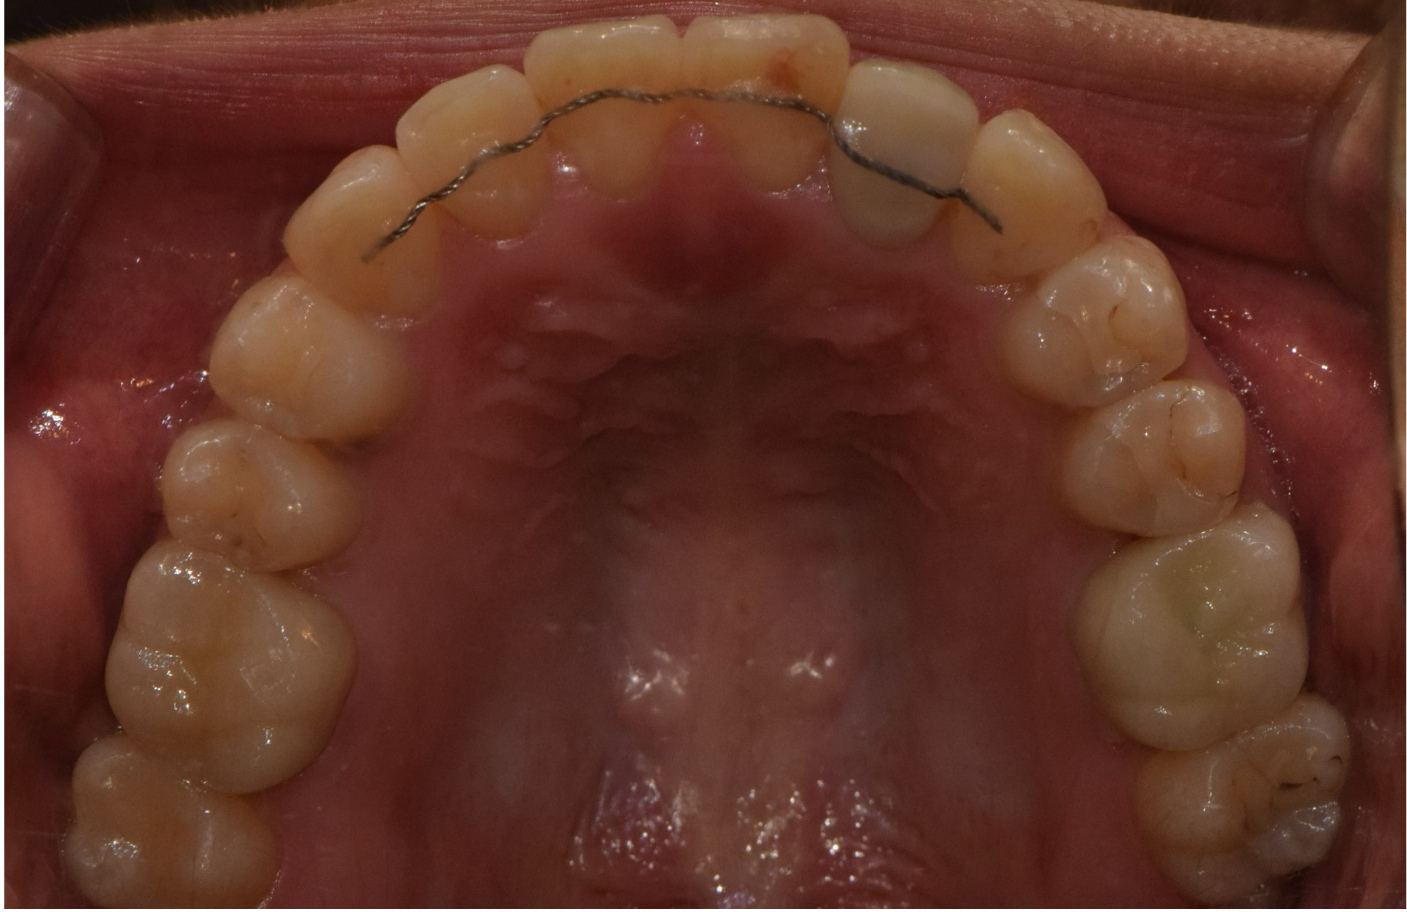

상악 악궁이 좁을 경우에는 하악을 편안하고, 안정적으로 수용하지 못하기 때문에 치아의 배열이 고르지 못하고, 이로 인해 돌출입, 주걱턱과 같은 문제가 생기게 됩니다. 이러한 경우 악궁확장을 통해 미리 증상을 예방하거나 이미 문제가 발생한 경우 시행하여 안정적이고, 바른 치아배열을 만들 수 있습니다. 아래사진은 주걱턱 개선을 위해 양악 수술을 할 줄 알고 큰 근심을 가진 환자를 상악궁 확장을 통한 비수술-비발치 교정으로 치료한 증례입니다.

악궁확장 후 변화